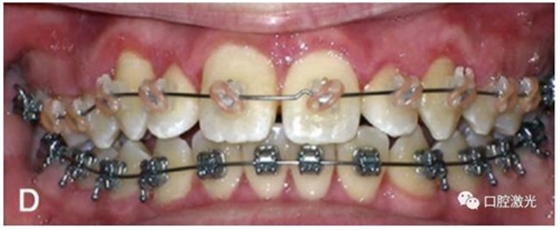

有時,會遇到一些口腔衛(wèi)生問題比較嚴重的患者,從而導(dǎo)致牙齦發(fā)炎而腫大。通過改善口腔衛(wèi)生環(huán)境,炎癥可以得到緩解,但增生的牙齦不一定都可以完全恢復(fù)。下圖的患者就存在口腔牙齦肥厚問題,同時左上部犬牙存在部分萌出的問題,右上部犬牙存在未萌出問題,這些問題都妨礙了托槽的粘接。因此,實施了全口腔的牙齦整形手術(shù)。去除了多余的牙齦組織,增加了犬牙的暴露面積,從而使托槽的粘接更為便利,同時也提升了患者保持口腔衛(wèi)生的狀況。

6周后效果